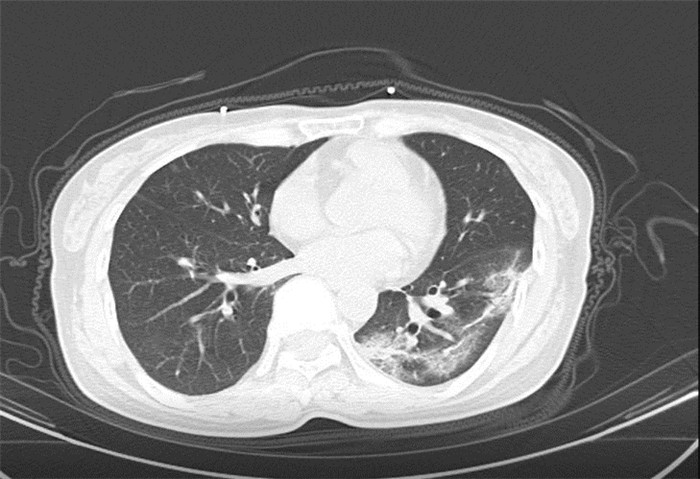

武漢大學中南醫(yī)院影像科副主任張笑春教授發(fā)現(xiàn),目前武漢市家庭聚集性發(fā)病較多,而且大多起病隱匿,一次甚至多次核酸陰性,無任何臨床癥狀,CT檢查卻已顯示為病毒性肺炎特征。

為了盡快篩查新型冠狀病毒肺炎患者,醫(yī)院會選擇影像診斷作為早期發(fā)現(xiàn)新型冠狀病毒感染的肺炎的重要一環(huán)。

CT為當前首選篩查與診斷的主要影像學手段,胸部CT的病毒性肺炎檢出率高。

方舟CT(CT Ark)可以滿足全面的臨床功能,配置16層、32層、64層、128層CT,實現(xiàn)了低劑量掃描要求,配合NDI微劑量迭代技術,智能毫安調控技術,使各種場合下、各部位低劑量掃描得以實現(xiàn);超高分辨率CT病灶靶掃描,使病灶的密度顯示更加精確,能夠顯示病灶內輕度的密度變化,有利于小病灶的密度定量分析和及時診斷。